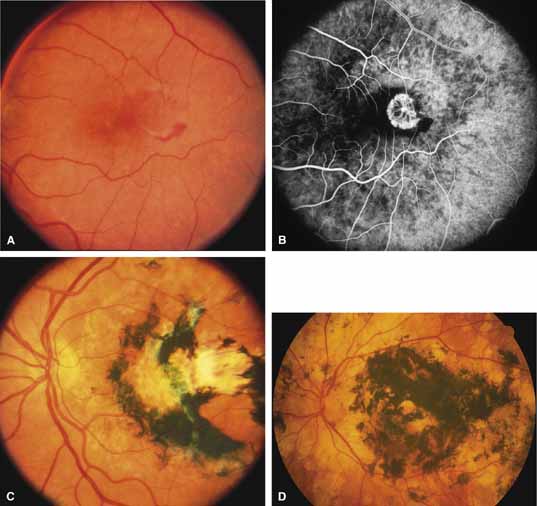

Bietti's crystalline dystrophy (MIM No. 210370) of the cornea and retina is an autosomal recessive disorder that is characterized by the presence of crystals of unknown composition in the stroma of the peripheral cornea and at several layers of the retina (Figs. 3A and 3B).23 The disease can be subdivided into regional and diffuse forms, and the lack of any reports of the two patterns in the same family suggests genetic heterogeneity and not just variable expressivity.24,25 The regional form begins in midlife as pericentral scotomas that cause difficulty reading and reduced central visual acuity. Peripheral retinal function is retained and the electroretinogram and electrooculogram are normal or near normal even in moderately advanced disease. The fundus appearance and fluorescein angiogram reveal regional loss of pigment epithelium and choriocapillaris limited to the posterior pole (Figs. 3C and 3D). The finding of abnormal crystals in leukocytes indicates that this is a systemic metabolic disorder.24

The diffuse form presents with loss of peripheral visual field, symptoms of poor night vision as well as reduced visual acuity, and diffuse loss of pigment epithelium and choriocapillaris on funduscopy (Fig. 4) and on fluorescein angiogram. The ERG is profoundly abnormal early in the course of the disease, and visual impairment eventually becomes much more severe in the diffuse than in the regional form of the disease.